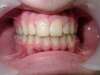

Supraclusion

AVANT